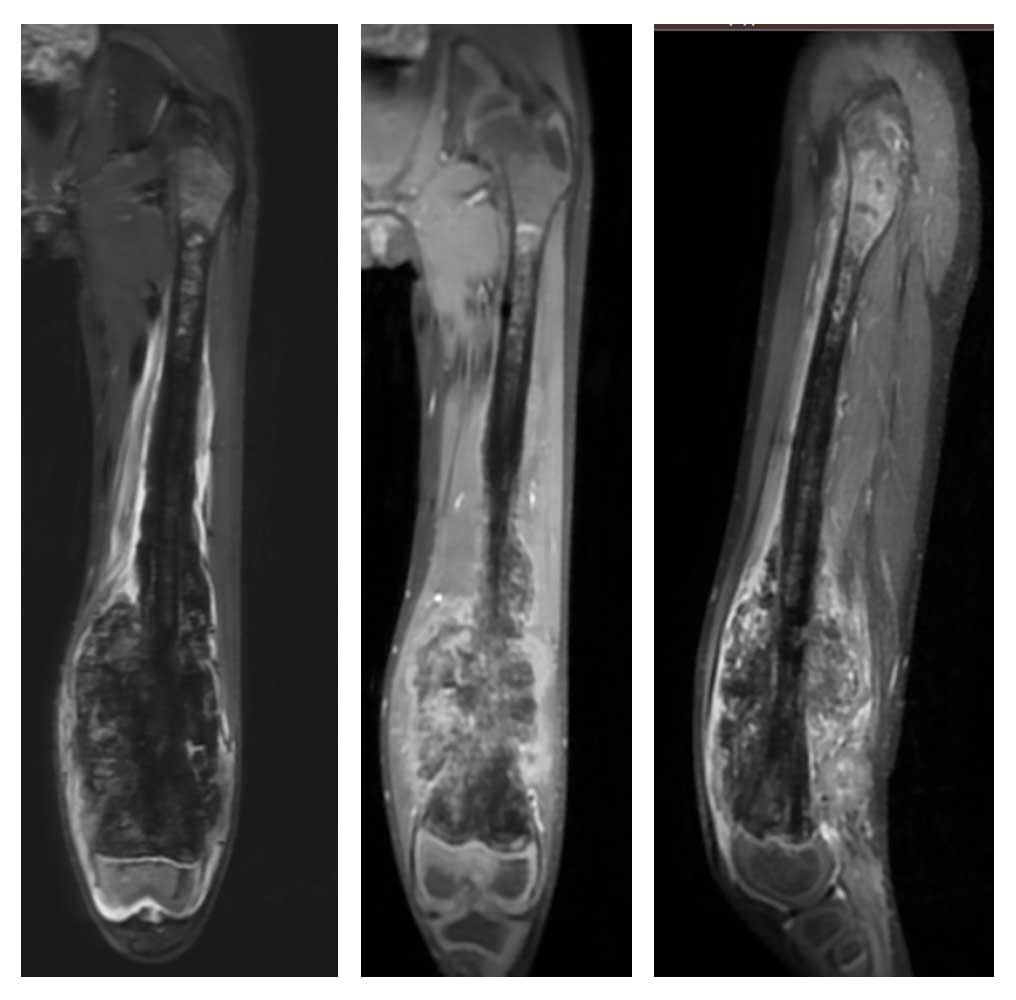

Ameliyat Öncesi: MR’da femurun tamamına yakınını dolduran distalde büyük kitle oluşturan çevreleyen ödemin eşlik ettiği düzensiz sınırlı tümör dokusu.